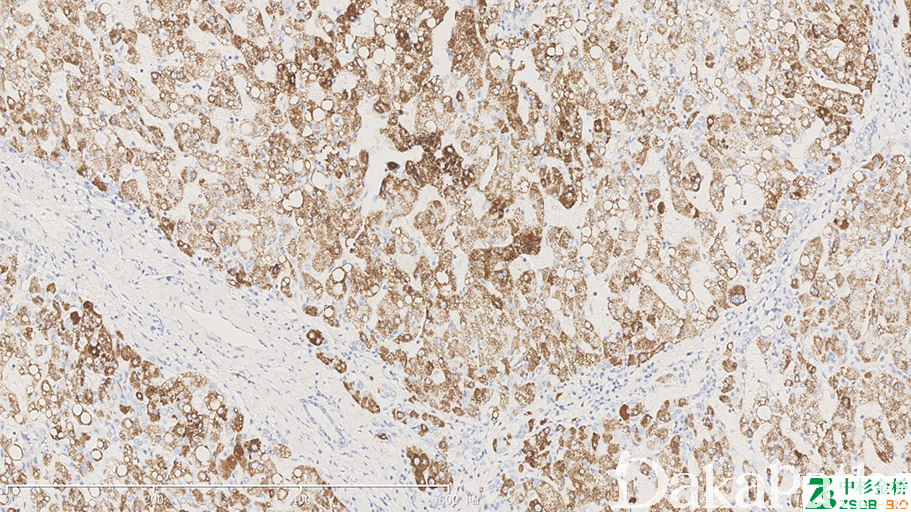

Hep-Par1

标记正常肝细胞、多数肝癌细胞。HCC 诊断中,HepPar1 是一种具有较高敏感性和特异性的标记物,它的特异性靶点在肝细胞的线粒体,可生产弥漫的颗粒状物质,胞质呈颗粒状。

信号定位: 胞质